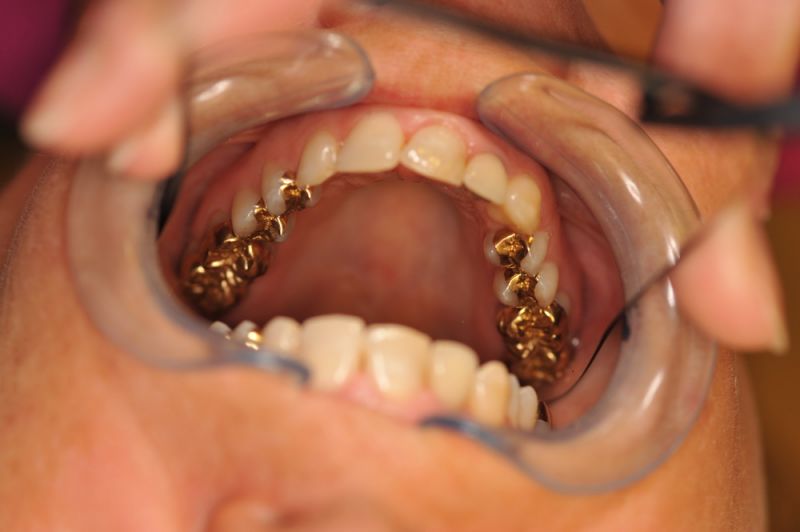

Patientin aus Uelzen zum Recall

Die Arbeit befindet sich seit 23 Jahren unverändert im Munde der Patientin!